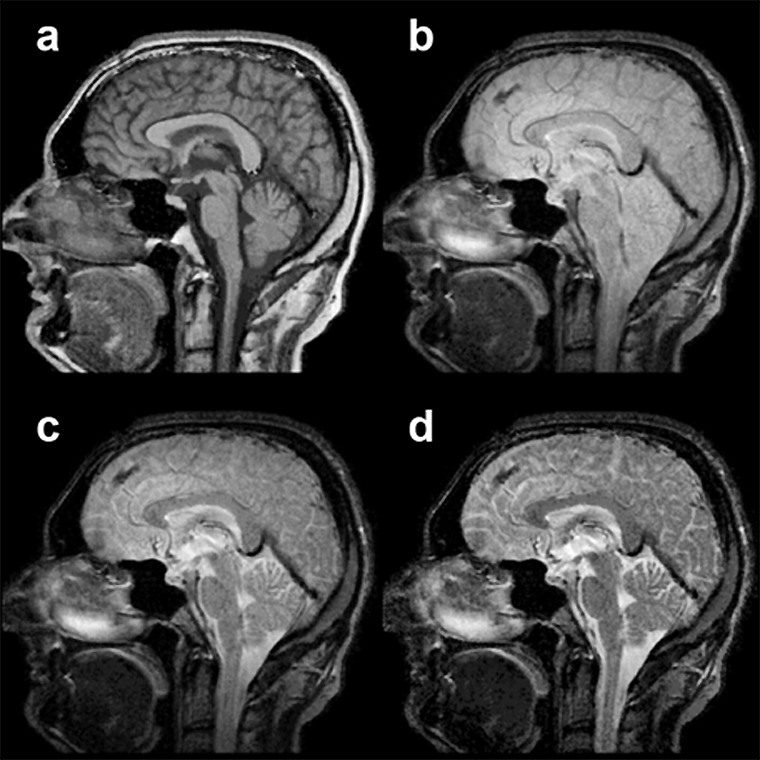

Figura 14-04:

Midsagittal slice through a normal brain. SE pulse se­quence, from (a) T1-weighted through (b) and (c) in­ter­me­di­a­te­ly weighted to (d) T2-weighted.

The fluid signal of CSF changes ac­cor­ding­ly, and the flowing blood in the straight si­nus stays black.